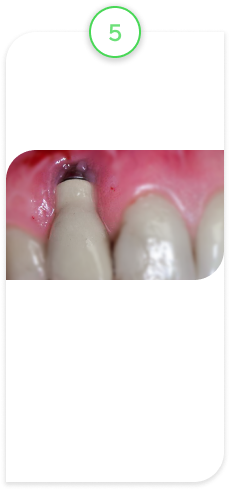

Случай из практики.

Наращивание десны

Пациент обратился с жалобами на оголенный корень зуба, повышенную чувствительность, на неэстетический вид зуба, так как зуб стал выглядеть длиннее, чем раньше.

После обследования поставили диагноз — рецессия десны.

Это патологическое состояние, при котором десна опускается вниз, корень зуба оголяется, появляется чувствительность зуба, эстетический дефект и возрастает риск развития другого патологического состояния — кариеса корня. В свою очередь, кариес корня — это показание к удалению зуба.

В данном клиническом случае провели микрохирургическую операцию по наращиванию десны с применением специального микроскопа. Это дало хороший, долгосрочный прогнозируемый результат.

ВАЖНО! Нужно понимать, что не у каждого оголенного корня можно нарастить десну. Ключевой фактор — стадия, на которой вы обратились. Есть стадии, на которых это невозможно, и единственным вариантом является УДАЛЕНИЕ ЗУБА!

Исходное состояние